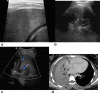

Cross-sectional imaging modalities like MRI and CT provide images of the chest which are easily understood by clinicians. However, these modalities may not always be available and are expensive. Lung ultrasonography (US) has therefore become an important tool in the hands of clinicians as an extension of the clinical exam, which has been underutilized by the radiologists. Reinforcement of the ALARA principle along with the dictum of "Image gently" have resulted in increased use of modalities which do not require radiation. Hence, ultrasound, which was earlier being used mainly to confirm the presence of pleural effusion as well as evaluate it and differentiate solid from cystic masses, is now being used to evaluate the lung as well. This review highlights the utility of ultrasound of the paediatric chest. It also describes the normal and abnormal appearances of the paediatric lung on ultrasound as well as the advantages and limitations of this modality.